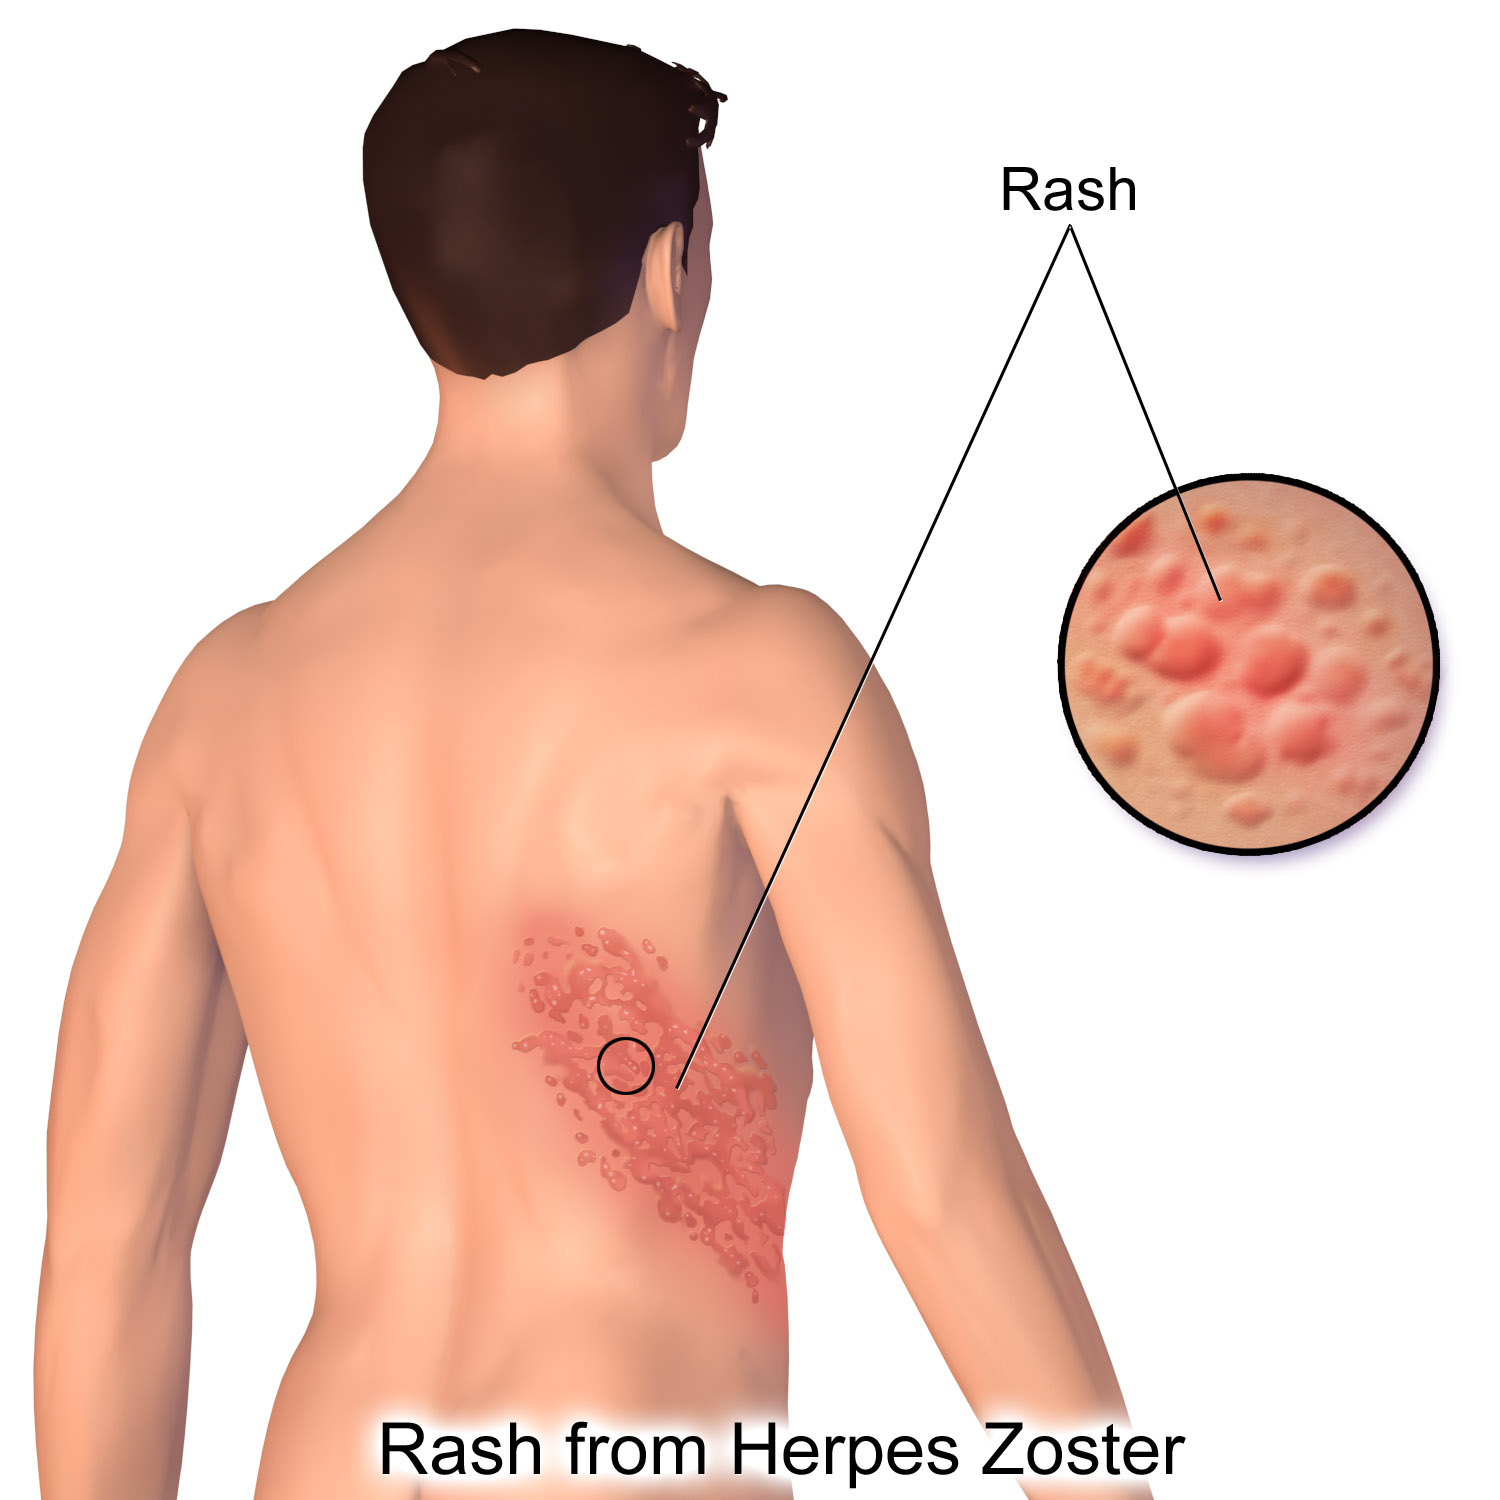

Медицинские снимки и изображения опоясывающего герпес вируса

Раздел: Фотодневник открытий